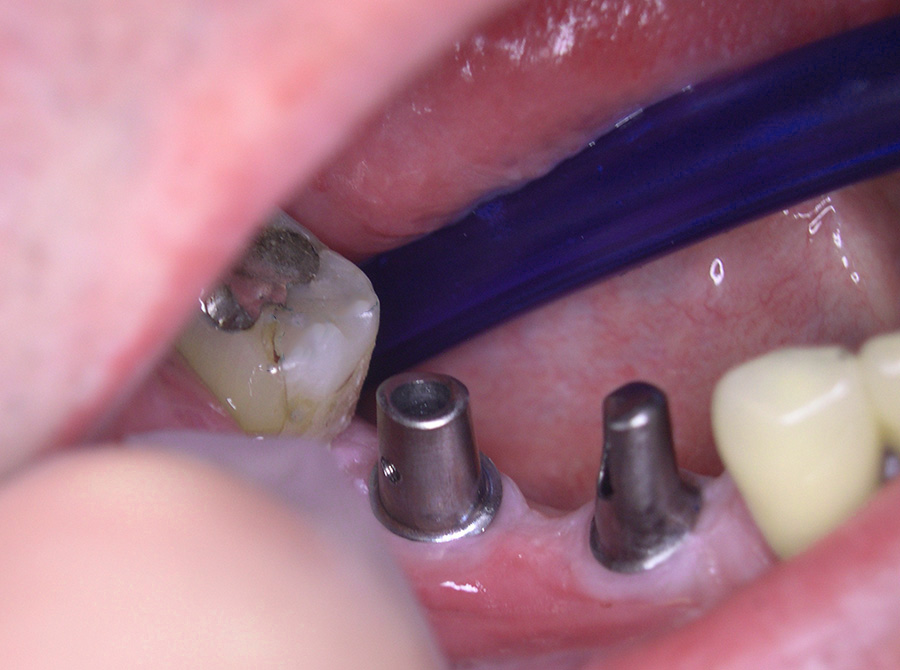

Der Einsatz moderner Zahnimplantate erweitert unser Behandlungsspektrum in verschiedener Hinsicht:

So können Lücken geschlossen werden, ohne dass gesunde Nachbarzähne beschliffen werden müssen und unnötig Zahnsubstanz abgetragen wird (Brückenversorgung).

Aber auch Prothesenträger profitieren von Implantaten, da durch diese herausnehmbarer Zahnersatz sicherer zu verankern ist, was die Lebensqualität bedeutend steigert.